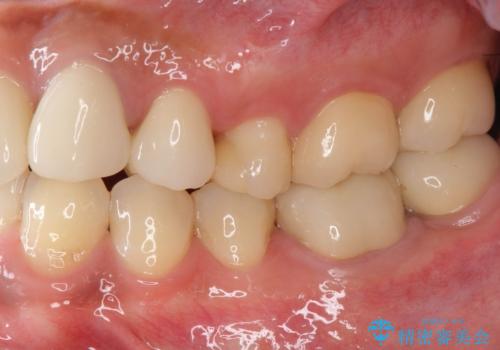

- 長年虫歯の治療を受け続けたことで銀歯・コンポジットレジン修復だらけになってしまい、今後の見た目や歯を大切にするためにセラミック治療矯正治療を希望され来院されました。

歯並びを整えたことで、歯ブラシのしやすさが向上し見た目も銀歯を全て除去したことで大きく改善して大変満足いただくことができました。